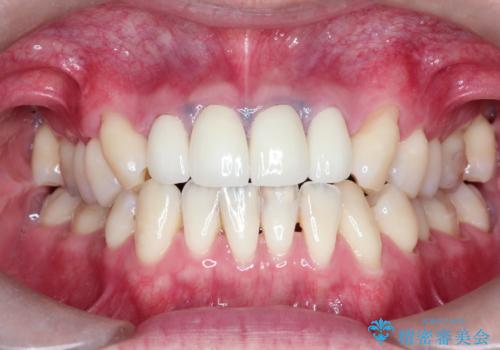

矯正治療で前歯の歯並びを整えてからセラミックほ装着する計画としました。

歯並びをかぶせ物のみで改善するのには限界があります。

矯正を併用することで、より審美的に良いかぶせ物を装着することが可能になります。